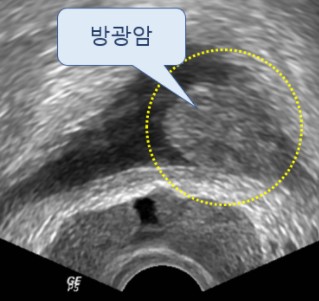

남자의 건강을 위협하는 대표 질병 중 한 가지는 전립선 질병이다. 전립선염은 남자의 50%가 일생에 한 번은 겪어볼 정도로 흔한 질병이 됐으며, 전립선암은 최근 20년간 20배 넘게 증가할 정도로 대중적인 질환이 되었는데요.